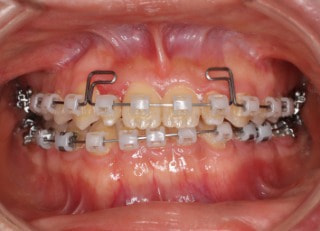

治療後(2年11ヶ月後)